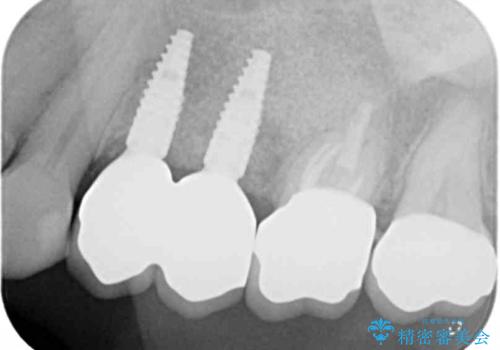

治療後に再発した虫歯や根管再治療に加え、穴の空き症状のある上顎左側小臼歯は抜去を行いインプラントによる機能回復治療を計画します。

X線写真検査ではわからない虫歯も外してみると再発していることがあります。虫歯を丁寧に取り除き、再発を防ぐべく精密なクラウンの作製を行うことが長期的な予後につながります。